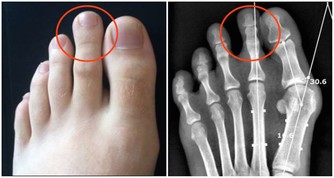

1.絕頂男盲目補腎越脫越嚴重

一些男性誤認為脫髮是腎虛所致,自己買些補腎的藥來吃,結果越吃脫髮越嚴重。雄性脫髮最好是早發現,早治療。預防脫髮除了注意休息和鍛鍊身體,在使用洗髮液的同時,也要注意,要加點水揉搓起泡沫了,再從發梢開始向上,如果你是短髮就不存在從發梢開始的問題了,從後腦勺向前揉搓即可。

如果使用護髮素和焗油膏,也不應該抹在頭皮上,抹在發梢和發中即可。脫髮嚴重的男性最好到醫院就診,在醫生的指導下用藥,米諾地爾和非那雄胺都有很好的效果。